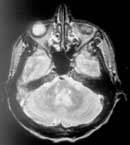

Данные МРТ головного и спинного мозга позволили выявить очаги снижения интенсивности сигнала (чаще перивентрикулярные, реже одиночные в ножках мозга, полушариях) в Т-1W режиме и одновременного повышения интенсивности сигнала в Т-2W режиме в начальном периоде РС у 53 (70,7%) в головном и у 41 (54,7%) - в спинном мозге. Несмотря на наличие четких клинических симптомов РС диагностическая значимость МРТ головного и спинного мозга в начальном периоде РС не высокая (Рис. 1, 2).

Рис. 1. Очаги демиелинизации в стволе головного мозга.